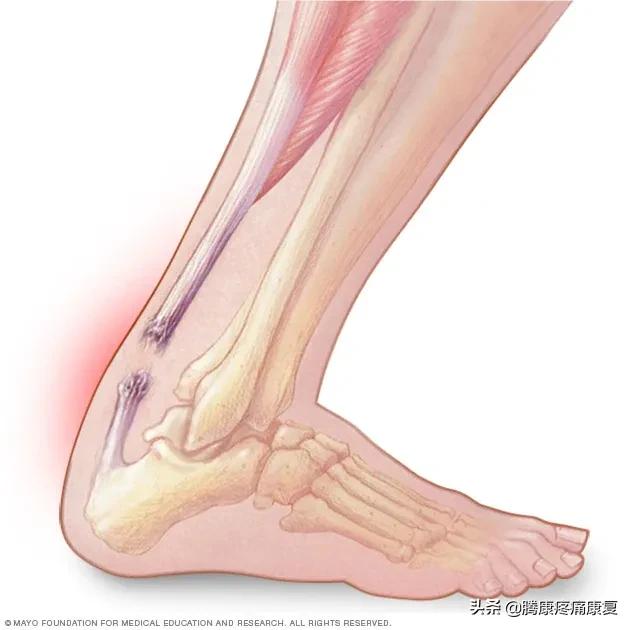

跟腱炎或断裂

跟腱是人体最大的肌腱,它位于腿部后侧,连接小腿肌肉和脚跟骨。

当肌腱受到刺激时,通常是由于过度使用,可能会感觉到腿后部的灼痛,通常就在脚跟上方。也可能有小腿疼痛和僵硬感,这就是众所周知的跟腱炎。

当跟腱肌腱撕裂时,腿后部可能会突然出现剧烈疼痛。腿可能很难承受任何重量。有些人在受伤时还会听到“砰”的一声。